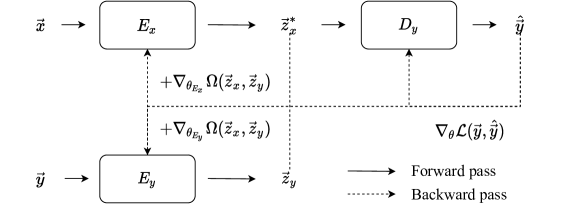

Mathematical operations, such as addition and subtraction, are performed over the EEG and fMRI feature representations, and , to map the original spaces onto encoded spaces that are identical in structure, and , respectively. This is performed in accordance with the methodology described in Appendix 0.A. To this end, architecture modules of Resnet-18 blocks is optimized using Calhas et al. [21] framework, which hyperparameterizes kernel and stride sizes, potentially differing from layer to layer. The heterogeneity of this convolutional layering structure is beneficial for the performance of the model according to Riad et al. [22]. Following, is processed by a densely connected layer with a linear activation to perform the decoding from the encoded representation onto the fMRI volume. Figure 1 illustrates the described neural processing pipeline. For the sake of simplicity, please consider .

The mean absolute error (MAE) is used as the loss function, , and the cosine distance between the latent representations of the EEG and fMRI was added as a regularization term, . MAE is known to be robust under limited data settings and the regularization term on latent representations forces the network to approximate the target representation at the earlier layers [29]. The regularization constant was set to and not optimized for the sake of proof of concept. Please recall the gradient computation illustrated in Figure 1.

using the complete neural flow, illustrated in Figure 1, that maps EEG to fMRI.